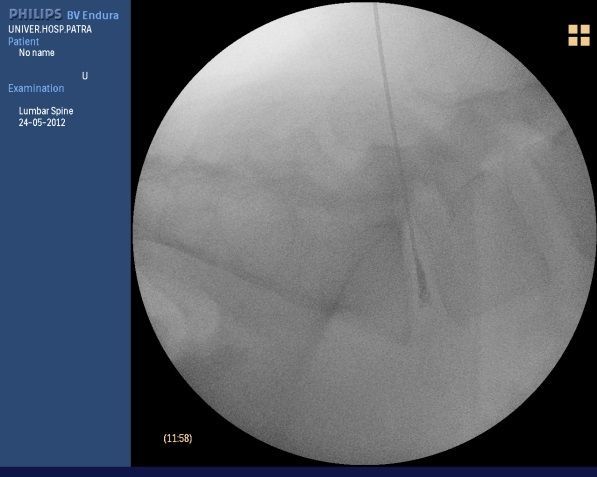

One of the most modern percutaneous techniques is the chemical destruction of the intervertebral disc nucleus pulposus with discogel. Discogel is a material in liquid form (ethanol solution in gel and contrast material). The technique is simple and easily tolerated by the patient. Under local anaesthesia, a needle is inserted into the intervertebral disc under radiological guidance and discogel is injected into the disc. The procedure takes 10 minutes. The patient then remains lying down for 2 hours and is discharged from the hospital. Pain relief is not immediate but a period of a few days is allowed for the patient to get relief. With this technique it is estimated that 60% of patients with severe radicular pain in the legs due to a small herniated disc can avoid surgery. This procedure is not indicated in large herniated discs where percutaneous microdiscectomy is usually required.

Discoplasty with discogel for herniated disc 05-1 interval.